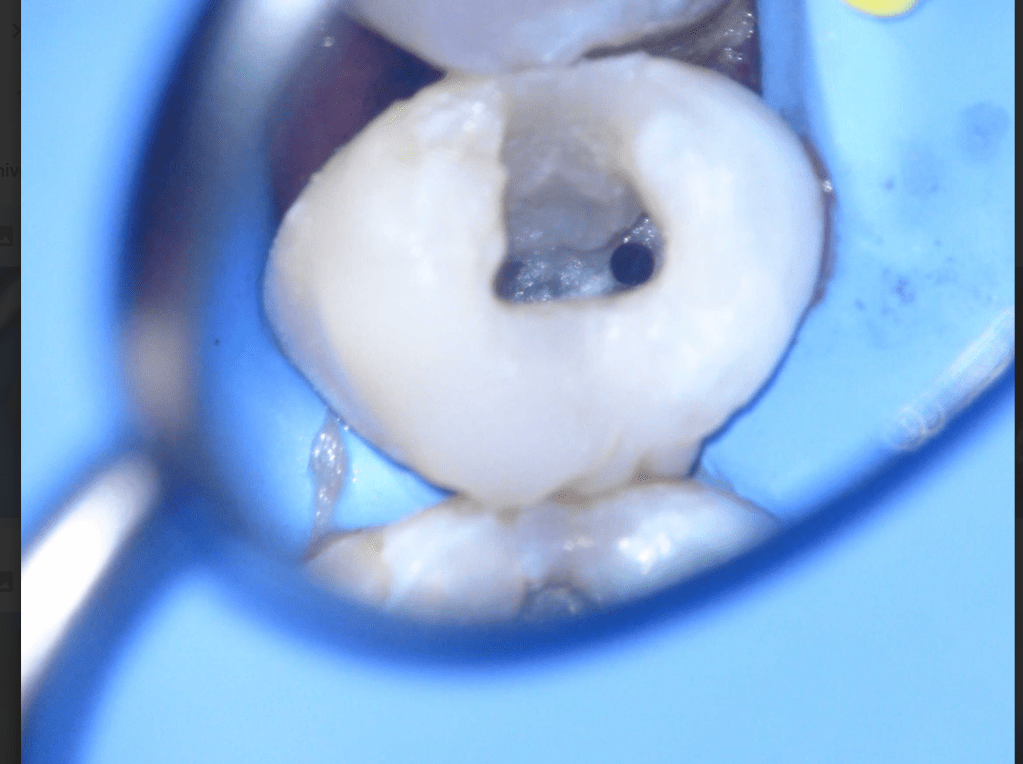

Fisura, remoción amalgama para explorar